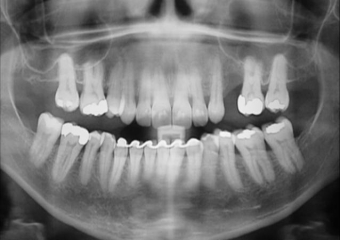

Raio X inicial, obsevando ausência de um pré molar superior à esquerda